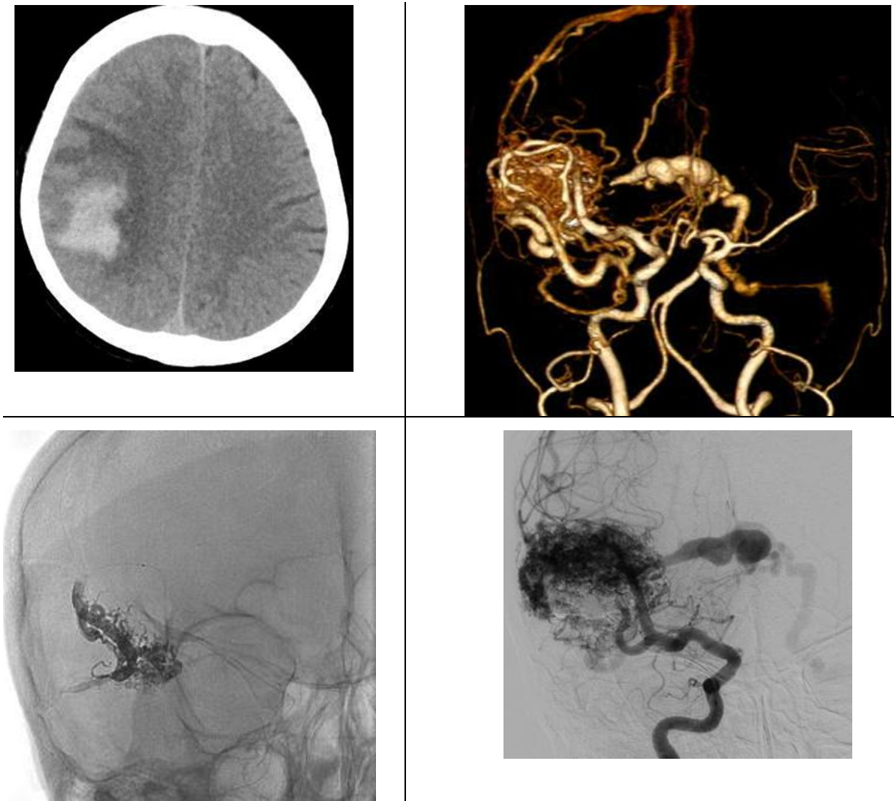

Một số nguyên nhân mạch máu gây xuất huyết não thường gặp trong thực hành lâm sàng bao gồm: phình động mạch não, dị dạng thông động tĩnh mạch não (AVM), dị dạng rò động tĩnh mạch màng cứng (dAVF), huyết khối xoang tĩnh mạch não.

Phình động mạch não

Phình động mạch não vỡ là nguyên nhân của 85% các ca chảy máu dưới nhện không do chấn thương.

Phình động mạch não được phân loại theo hình dạng bao gồm phình hình túi (saccular aneurysm), phình hình thoi (fusiform aneurysm), phình do lóc tách mạch (dissecting aneurysm), phình dạng fusi-sacciform trong bệnh lý giãn phình (dolichoectasia), phình dạng bọng nước (blister aneurysm). Phình hình túi chiếm phần lớn trong số phình mạch não. Phình hình túi được chia làm hai loại liên quan đến việc điều trị bao gồm phình cổ hẹp và phình cổ rộng. Phình cổ rộng được định nghĩa là túi phình có cổ ≥ 4mm hoặc tỉ lệ đường kính đáy/cổ <1.5.

Việc chẩn đoán và điều trị gây tắc phình động mạch não vỡ được thực hiện theo các khuyến cáo của hiệp hội đột quỵ Châu Âu và Mỹ. Chẩn đoán phình mạch não vỡ dựa vào chụp CT mạch máu, cộng hưởng từ mạch máu hoặc chụp mạch số hóa xóa nền (DSA) trong đó chụp DSA là tiêu chuẩn vàng để chẩn đoán.

Hai phương pháp được lựa chọn bao gồm phẫu thuật hoặc can thiệp nội mạch. Việc lựa chọn phương pháp điều trị tùy thuộc vào hình dạng, vị trí, kích thước túi phình cũng như tuổi, các bệnh lý đi kèm cũng như là lựa chọn của bệnh nhân. Thử nghiệm lâm sàng ISAT (International Subarachonoid Aneurysm Trial) khuyên chọn can thiệp nội mạch nút coils nếu túi phình vỡ có thể được điều trị bởi cả hai phương pháp là như nhau. Hơn nữa, các túi phình có cổ nhỏ hay ở vòng tuần hoàn sau, bệnh nhân cao tuổi thì nên điều trị bằng nút coils. Các yếu tố ủng hộ phẫu thuật bao gồm các túi phình có cổ rộng, có nhánh mạch tách từ túi phình, phình động mạch não giữa, phình quanh trai hoặc bệnh nhân có khối máu tụ nhu mô đi kèm.

Trong can thiệp nội mạch, phương pháp nút coils đơn thuần được ưu tiên lựa chọn đối với phình hình túi cổ hẹp. Đối với phình hình túi cổ rộng thì có thể lựa chọn can thiệp nút coils có bóng chẹn cổ hoặc nút coils có stent hỗ trợ hoặc đặt lồng WEB. Đối với phình hình thoi, phình lóc tách đã vỡ thì phương pháp bảo tồn (bằng đặt stent chuyển hướng dòng chảy) hoặc phương pháp gây tắc mạch nuôi có hiệu quả gây tắc túi phình tương tự nhau tuy nhiên phương pháp bảo tồn nên được ưu tiên nếu có khả năng thực hiện. Đối với phình hình bọng nước (blister aneurysm), việc điều trị hiện nay còn gặp nhiều khó khăn và còn nhiều tranh cãi thì đặt stent chuyển dòng hiện đang là phương pháp được cân nhắc đầu tay để điều trị.

Thông động-tĩnh mạch não (AVM)

Thái độ xử trí đối với dị dạng thông động-tĩnh mạch não đã được hiệp hội Tim mạch và đột quỵ Hoa Kỳ đưa ra vào năm 2017. Nút mạch đối với dị dạng AVM có xuất huyết não cấp thường đặt ra để điều trị chảy máu do phình mạch cạnh ổ nidus dị dạng hoặc nút tắc chọn lọc điểm chảy máu giảm nguy cơ chảy máu tái phát. Sau giai đoạn cấp khi mà khối máu tụ đã tiêu hết (khoảng 4-6 tuần), thì việc nút mạch điều trị dị dạng AVM tùy thuộc vào mục tiêu cụ thể cho từng bệnh nhân bao gồm nút mạch triệt để dị dạng (qua đường động mạch hoặc tĩnh mạch), nút mạch giảm một phần thể tích nidus trước mổ giúp giảm nguy cơ phẫu thuật hoặc nút mạch một phần dị dạng phối hợp với xạ phẫu.